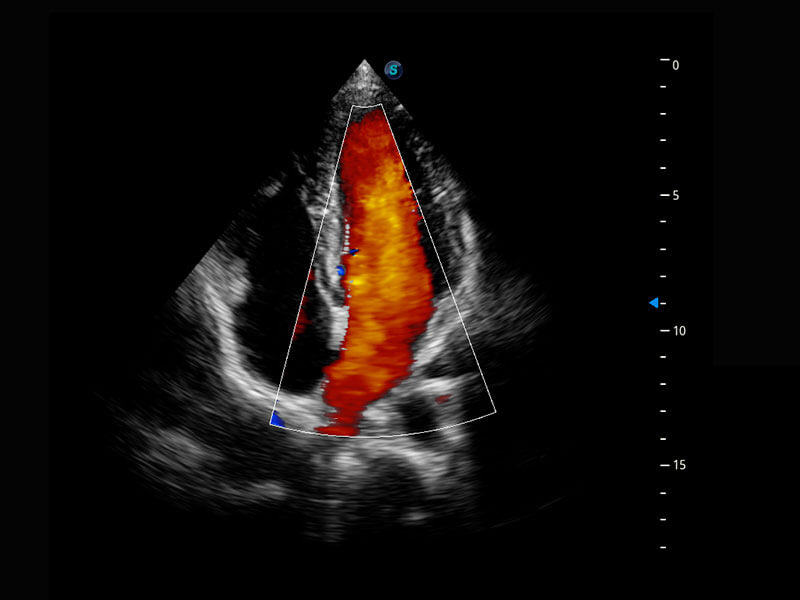

四腔切面

四腔心血流